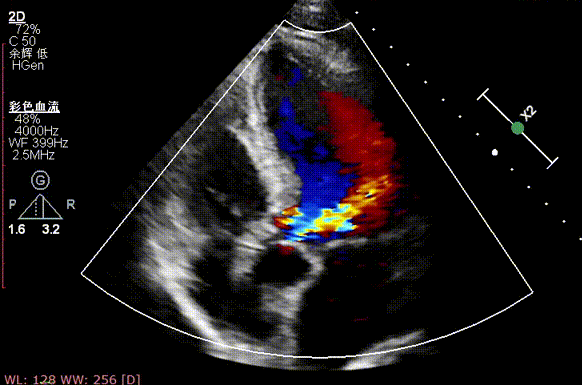

术前超声

术后超声